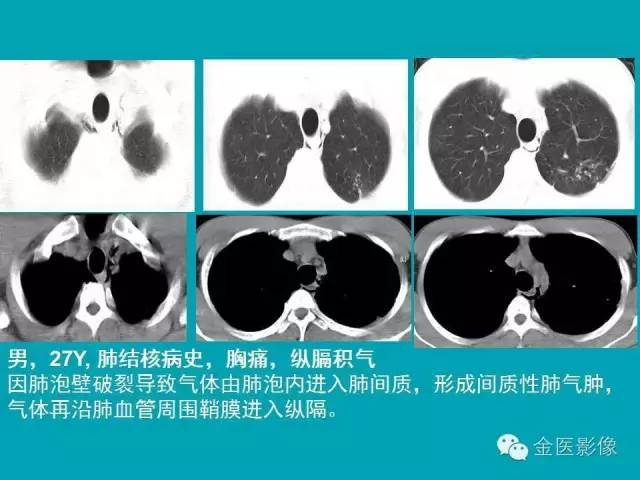

纵隔气肿的影像学表现